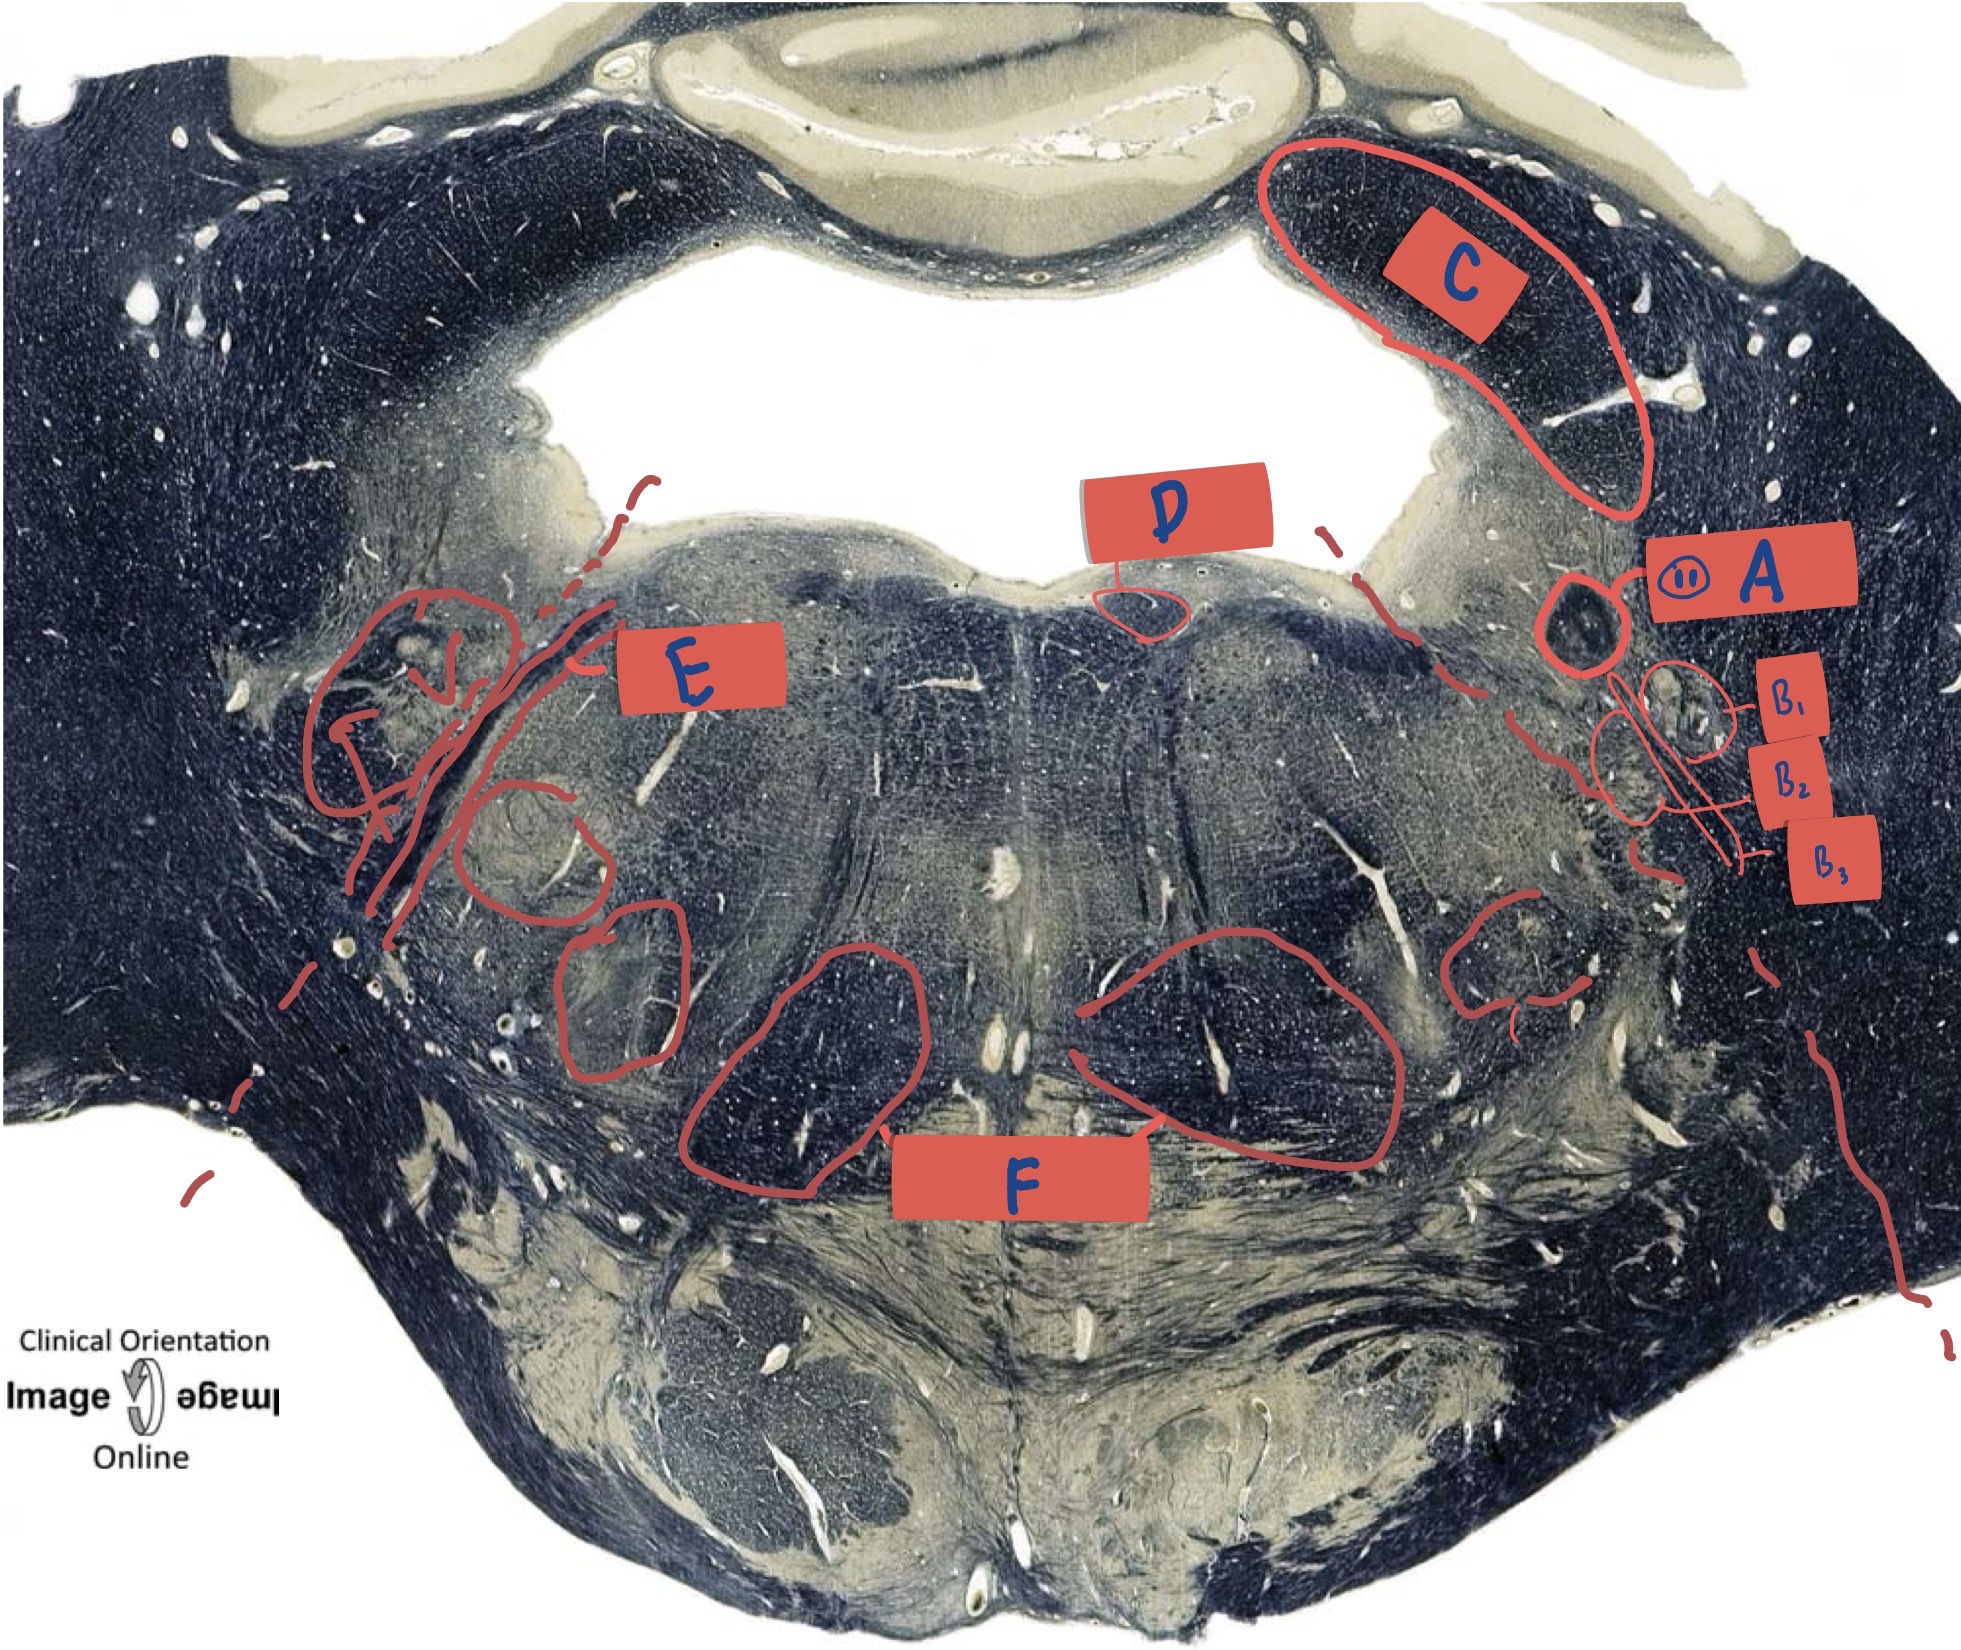

What is A?

Dorsal cochlear nucleus

What is B?

Restiform body

What is C?

Vestibular nucleus

What is D?

Nucleus prepositus

What is E?

medial longitudinal fasciculus

What is F?

Spinal trigeminal tract